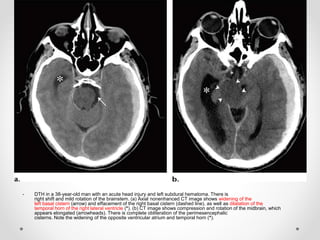

- DTH in a 38-year-old man with an acute head injury and left subdural hematoma. There is

right shift and mild rotation of the brainstem. (a) Axial nonenhanced CT image shows widening of the

left basal cistern (arrow) and effacement of the right basal cistern (dashed line), as well as dilatation of the

temporal horn of the right lateral ventricle (*). (b) CT image shows compression and rotation of the midbrain, which

appears elongated (arrowheads). There is complete obliteration of the perimesencephalic

cisterns. Note the widening of the opposite ventricular atrium and temporal horn (*).